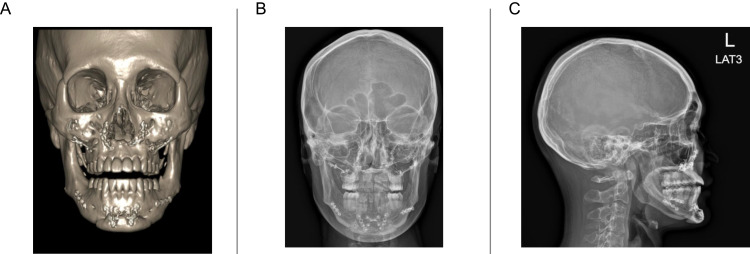

Case presentation: This report describes the case of a 28-year-old Thai male, who received titanium implants in the mandible bone, the mandible chin, the maxillary bone and the zygoma bone, seven years before. Because of his wish for a more sculpted and lifted facial appearance, the patient was treated with Ulthera Legacy in 2021 and with Ulthera Prime in 2024. With Ulthera Prime, visualization has significantly improved, which decreased the need to skip areas, leading to improved, more consistent results.